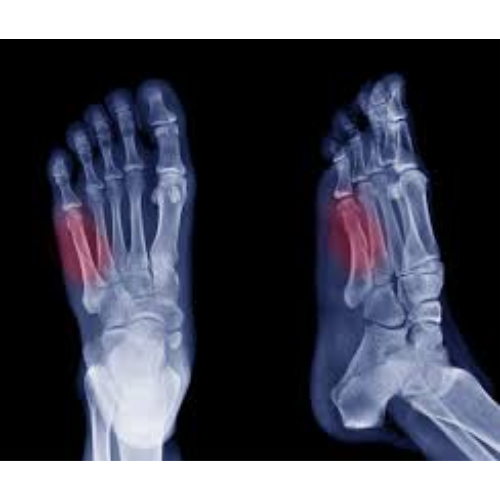

Hand & Foot Fractures

Hand and foot fractures are breaks in the bones of the hands or feet, commonly caused by falls, sports injuries, accidents or direct trauma. They can range from simple cracks to complex fractures involving multiple bones or joints. Treatment varies from splints and casts to surgical fixation, depending on the severity.

Who Needs It?

• Individuals with pain, swelling or bruising after injury to the hand or foot.

• Patients unable to move, grip or bear weight on the affected limb.

• Those with visible deformity, misalignment  or instability of the bones.

• Patients whose fractures require surgical intervention to restore proper function.

Benefits:

• Reduces pain and prevents further injury or deformity.

• Ensures proper bone healing and joint alignment.

• Restores hand dexterity or foot mobility, allowing return to daily activities.

• Minimizes long-term complications such as arthritis, stiffness or chronic pain.